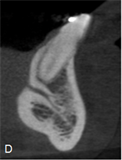

The following measurements were performed: longest width of the genial canal (W) or (D); longest length of the genial canal in relation to the alveolar bone crest (L) or (L1); (D1) or (L2), which was performed between the uppermost portion of the genial plexus and the alveolar bone crest (for dentate patients the reference was the buccal bone crest); shortest distance from the genial plexus to the buccal cortical bone (D2) or (L3), which was performed between the most vestibular portion of the genial plexus and the buccal cortical bone; (D3) or (L4), which was performed between the lowest portion of the genial plexus and the cortical part of the mandible base (Figures 1(B)-(D)).

Figure 2(A) is the initial parasagittal tomographic image of a dentate patient. Figure 2(B) Is the tomographic image of the paranasal sinuses in which the largest. Length of the genital canal (L or L1). Figure 2(C) is the parasagittal tomographic image in which the largest. The diameter of the genital plexus (W or D). Figure 2(D) is the tomographic image in which the measurement of the shortest distance from the plexus to alveolar bone crest (D1 or L2), shorter distance from the plexus to the buccal cortex (D2 or L3), and less distance from the plexus to the base of the mandible (D3 or L4).

Figure 1. Tomographic images, diameters and distances of the canal and plexus. (A) Parasagittal tomographic image; (B) Canal diameter; (C) Distance from the genial plexus to the cortical bone; (D) Initial parasagittal tomographic image, central incisor tooth. Source: Own Authorship. Caption: Parasagittal tomographic image measuring the length (A) canal diameter (B) and distances as follows: (L1) of the genial canal; (L2) distance from the genial plexus to the alveolar bone crest, (L3) distance from the genial plexus to the buccal cortical bone and the base of the mandible (L4) (C), initial parasagittal tomographic image (D). Figure 1 (A) Parasagittal section of the CBCT used to perform measurements. (B) Longest width of the genial canal (W). (C) longest length of the genial canal (L). (D) Shortest distance from the genial plexus to the alveolar bone crest (D1); shortest distance from the genial plexus to the buccal cortical bone (D2); shortest distance from the genial canal relative to the base of the mandible (D3).